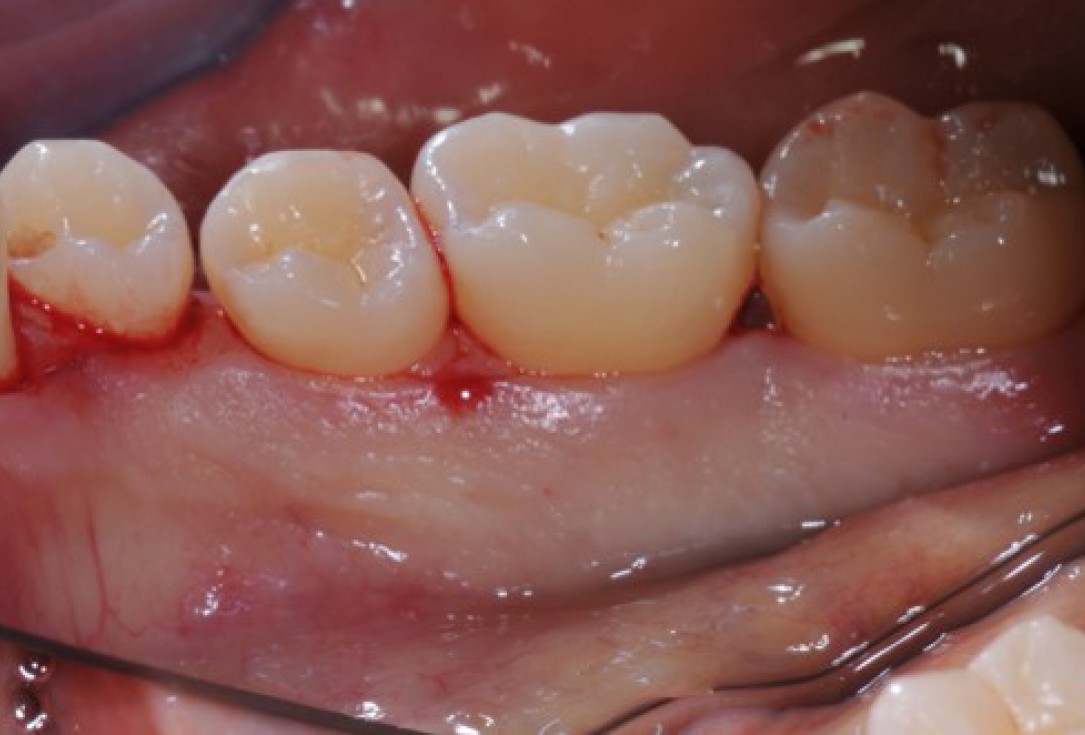

Radiographic view before periodontal regenerative therapy with Straumann® Emdogain®. A deep intrabony defect appeared mesially and distally on the left mandibular first premolar. Pre-surgical probing measured 8 mm. The defect morphology presented as well-contained.